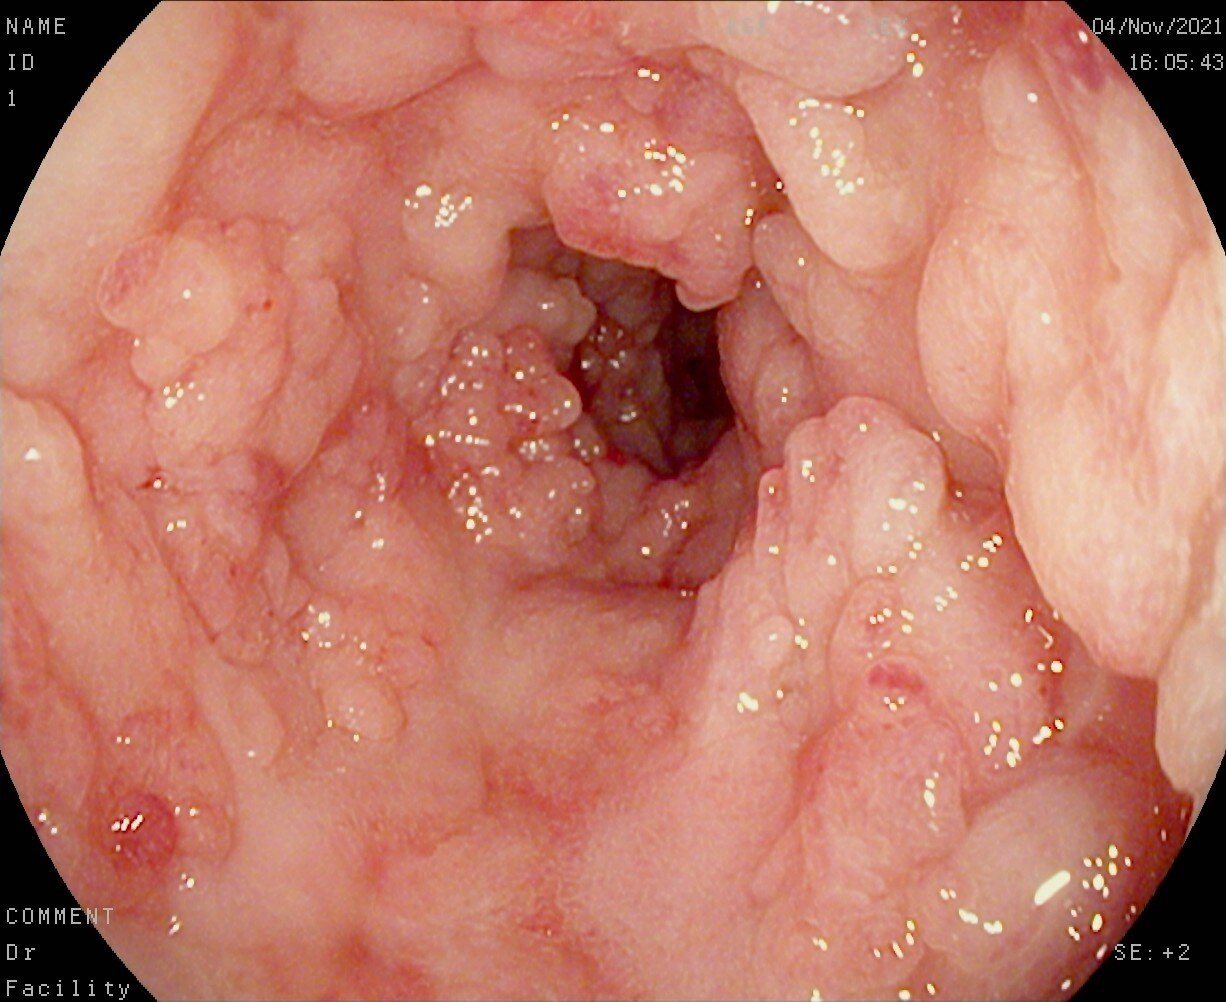

在肠镜的冷光下,我看到了克罗恩病的痕迹,那些扭曲的肠道,就像是被战争摧残过的土地。每一次看到这些图片,我的心都紧缩成一团,仿佛能感受到那些患者在病痛中的挣扎。...

在这个充满不确定的世界里,每个人都有自己的战斗。而我,一个名叫克罗恩的普通人,正经历着我生命中最艰难却又最值得纪念的时期。克罗恩,这个名字现在对我来说,不仅仅是一个标签...

哎呀,说到克罗恩病,这可不是什么轻松的话题。这病啊,就像个调皮的小鬼,时不时就来捣乱,让人吃不下饭,肚子还疼得要命。可有时候,光靠吃药打针,还真对付不了这个小鬼。这时候...